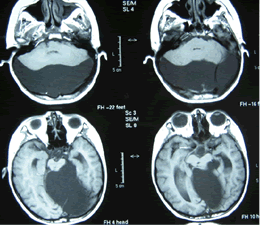

蛛網膜囊腫MRI表現CT 及 MRI 是蛛網膜囊腫最佳的診斷方法, 不但可以明確蛛網膜囊腫的部位、體積以及與周圍結構的關係,還能做出定性診斷。X線顯示蛛網膜囊腫鄰近骨質變薄、隆起或內板呈腦回壓跡樣凹陷等非特異性表現可作為輔助診斷。

1、CT 掃描顯示邊緣光滑、輪廓清晰、無鈣化、位於腦質外類似腦脊液密度的囊性病變 , CT 值為 4 ~ 8Hu , 周圍無水腫帶 , 造影劑無強化效應。毗鄰腦組織受壓,但一般多無中線移位。一些特殊部位如鞍上、四疊體的病變壓迫室間孔或導水管時可致腦室擴大、腦積水改變。